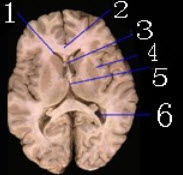

图为基底区大脑横断面,分别标出如图所示1_______________2_______________3_____________4___________5____________6_______________部位。